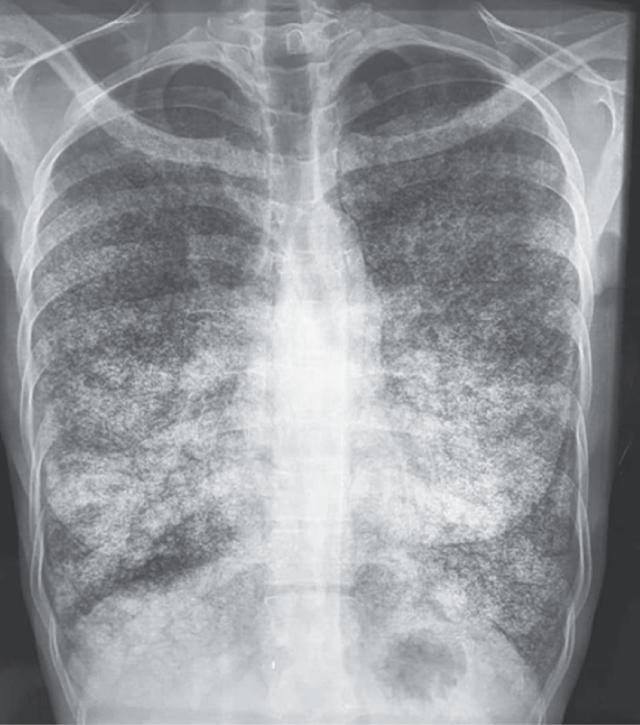

Фиброз с отеком